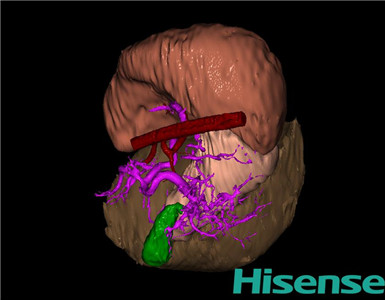

CT结果输入海信CAS系统后行3D重建及手术规划后,行手术治疗,术中证实为先天性门脉高压:

术前三维重建及手术方案设计:

将0.625mm双源薄层CT资料的静脉期和动脉期Dicom格式文件导入海信CAS系统。

通过调节窗宽窗位调整CT序号,对肝实质,胆囊,下腔静脉,肿瘤,肝动脉、门静脉及肝静脉等进行三维重建;系统自动计算肝脏体积。

术前三维重建:

重建图片